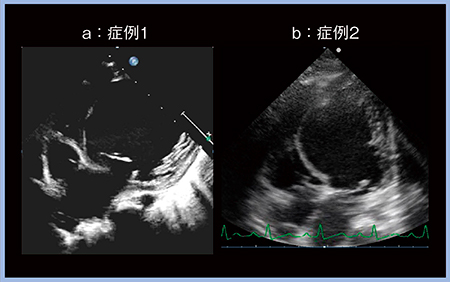

小児でe’波,DT,E/e’を検討すると,弛緩が悪くなるほどe’波は小さくなり,stiffnessが上がるほどDTが短くなり,EDPが上がるほどE/e’が大きくなるが,実際にはバラツキが非常に大きい2)。僧帽弁流入波形は,拡張能の悪化に伴いE/Aはいったん1を下回ってから再び上昇し,DTは逆にいったん上昇してから再び低下し,e’波は拡張能の悪化に伴い単調に低下すると言われている1)。僧帽弁流入波形から拡張能の悪化の程度を見ると,4つに分類できるが(図1a〜d),実際の小児の2症例(症例1,2)の波形(図1下段)はどちらもDTが非常に短く,bとdの両方の特徴を持つ波形である。したがって,実際の症例をこの4パターンのみで語ることはできない。症例1,2は同様の流入波形だが,両者の重症度は大きく異なる。症例1は肺うっ血が強く,BNPが1300〜6500pg/mLときわめて高値だが,症例2は60〜130pg/mLとやや高値であるものの,心不全入院はない。超音波の心尖部四腔断面像(図2)では,症例2も健常例より左室機能が低下しているが,右室機能は良好であり,全体として代償されていると考えられる(b)。

図1 僧帽弁流入波形のバターン分類と実際の症例の波形(症例1,2)

図2 心尖部四腔断面像(症例1,2)